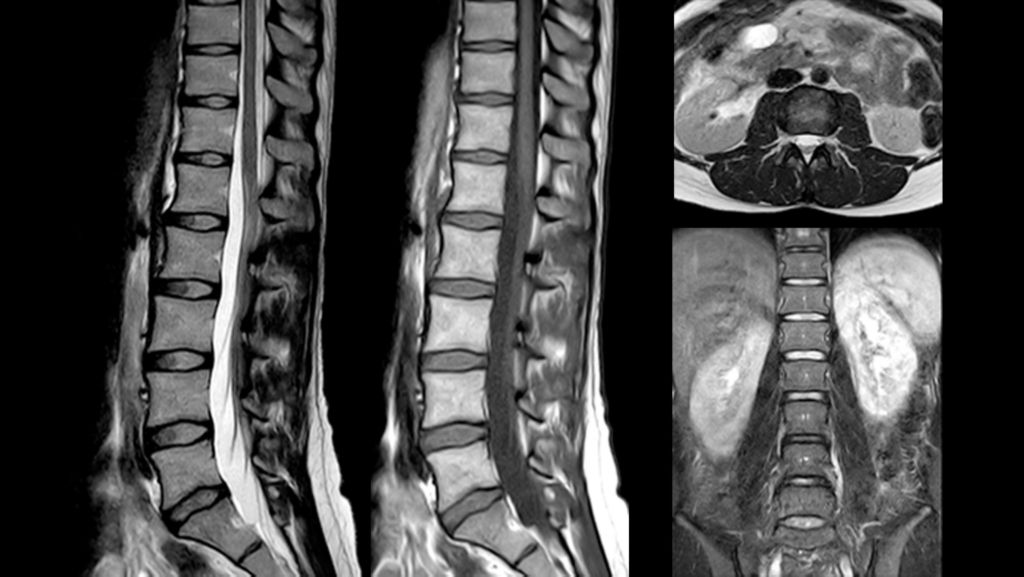

• 3D T2w TSE SpineVIEW

3D T2w TSE SpineVIEW

• Lumbar Spine

Lumbar Spine